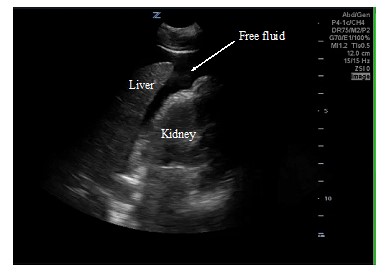

An 18-year-old male was brought in by EMS with a penetrating stab wound to his left buttock from an unknown weapon. Blood was oozing from the stab wound entry site, but he was hemodynamically stable. Shortly after arrival to the emergency department, he developed frank hematuria. An initial FAST exam revealed a large clot within the bladder walls (Fig. 1) but was negative for intraabdominal free fluid. A large hematuria catheter was placed by Urology to evacuate this clot. CT and CT angiogram of the abdomen and pelvis revealed active bleeding within and adjacent to the left posterior bladder wall, as well as a clot filled bladder and a deep pelvic hematoma displacing the rectum. A CT cystogram revealed no filling defect within the distal ureters or extravasation of contrast to suggest intra- or extra-peritoneal bladder rupture. After CT imaging, Urology copiously irrigated the bladder with normal saline to remove the clot. During irrigation, the patient developed significant abdominal pain and distension. A repeat FAST exam was performed revealing free fluid in the right upper quadrant (Fig. 2), left upper quadrant (Fig. 3), and pelvis (Fig. 4). The pelvic view also revealed an enhanced peritoneal stripe sign (Fig. 4) suggesting pneumoperitoneum.

Figure 2. RUQ view of the repeat FAST. Anechoic free fluid is seen in Morrison’s pouch and surrounding the tip of the liver.